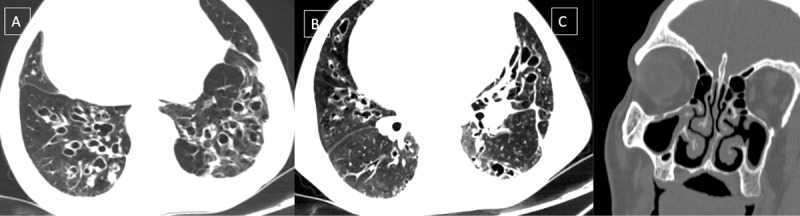

Incidental detection of polysplenia associated with situs inversus totalis in an adult is rarely reported in literature.12 "Heterotaxy" refers to a wide spectrum of anomalies involving dysmorphism of thoracoabdominal organs across the right-left axis of the body. Polysplenia is observed in left isomerism along with bilateral bilobed bronchi and bilateral morphologic left atria. However, in this case, polysplenia was present without isomerism.